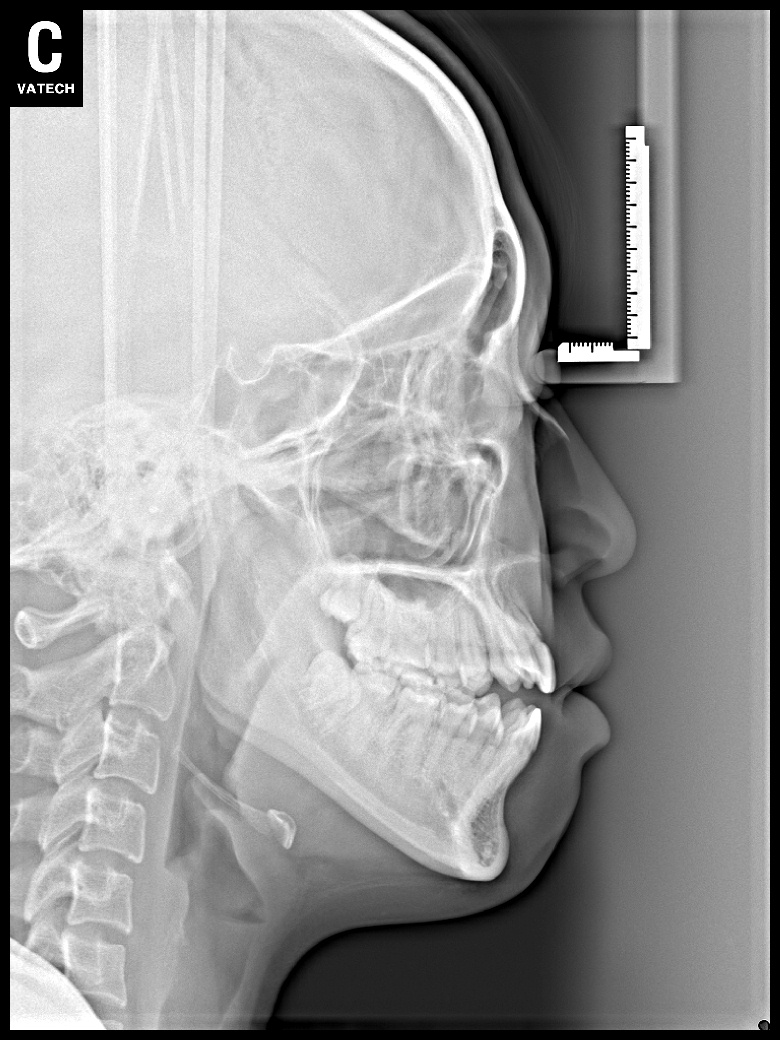

치료 전 사진입니다.